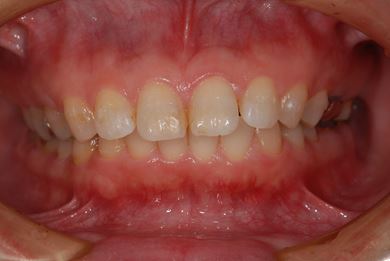

抜歯即日スピードインプラント治療+セラミック治療+歯肉歯槽骨整形術

| 治療方針 | 左下欠損部と保存不能の歯を抜歯し、インプラント治療にて機能的・審美的回復を行う。 | ||||||||||||||||||||||||||||||||

| 治療内容 | インプラント2本(抜歯即日スピードインプラント)、ハイブリッドセラミッククラウン2本、歯肉歯槽骨整形術 | ||||||||||||||||||||||||||||||||